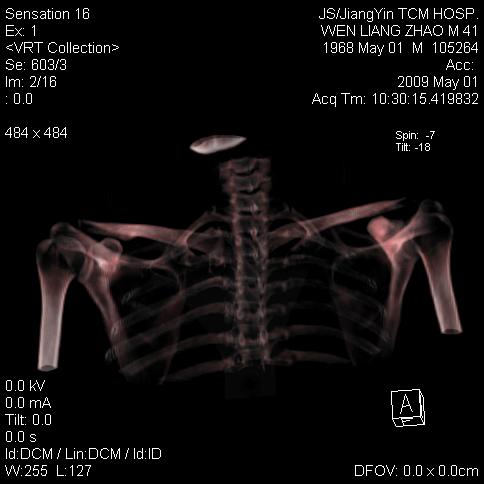

标题: CT19762:左侧喙突处压痛二年。考虑骨样骨瘤。 [打印本页]

标题: CT19762:左侧喙突处压痛二年。考虑骨样骨瘤。

左侧喙突处压痛二年。考虑骨样骨瘤。